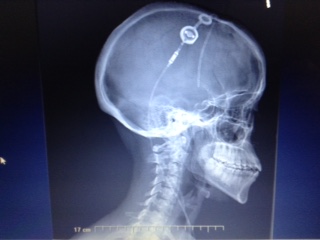

| X Ray image of my shunt from 2016. |

At least last weekend was better. This week my shunt has been misbehaving causing pain, throbbing sensations during different days. Today has been the worst day so far. (aside from when the eclipse happened over the summer. ) I was up off and on during the early morning hours from shunt pain. The only reason why I didn’t stay in bed with my head buried underneath a pillow was because I’m suppose to volunteer for a few hours this morning into the early afternoon. I hope I feel better when I return home later today. I checked the weather report and see there will be rain in my area this evening. As mentioned before, my shunt ( like many others ) predicts and reacts to the weather. I also have right eye pain this morning from the TMJ and some nausea from the shunt. At least the shunt is not beeping like it did in 2016.